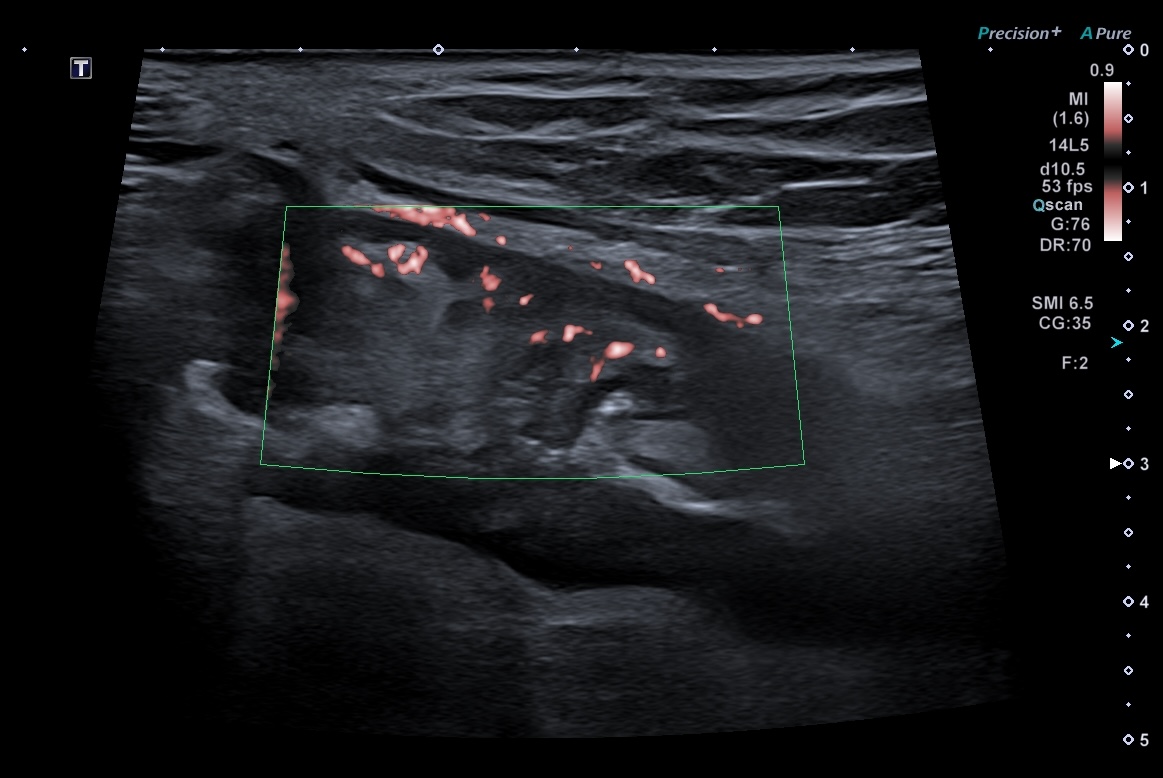

- Limberg 2 signaux nombreux et plus longs dans la paroi Vascularisation modérée avec plusieurs signaux Doppler visibles dans la paroi intestinale, (= inflammation modérée)

Doppler paroi + graisse

Activité Doppler limitée à la paroi, intense

- spots longs et multiples (limités à la paroi)

Il exite différents doppler qui peuvent tous être utilisés pour mesurer l'activité inflammatoire de la paroi intestinale.

- Le Doppler Couleur (qui enregistre la direction des flux (rouge se rapproche de la sonde et bleu s'éloigne de la sonde)

- Le Doppler Energie (qui ne mesure que les flux d'une seule couleur)

- La microcirculation (fournie par certains constructeurs)